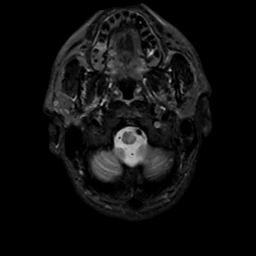

MR Study #1, February 10, 1991 -- Slice #3

[Home][Help][Clinical][Tour 1][Tour 2] Slice 3